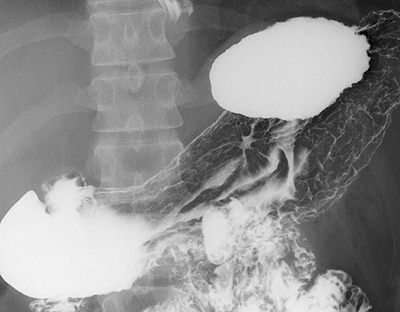

X線透視検査は、よく知られている胃のバリウム検査はじめ、食道、小腸、大腸といった消化管の癌の診断に用いられています。当院の透視装置は平面検出器(FPD: Flat Panel Detector)搭載X線TV装置であり、このFPD装置で撮影された画像は、直接、画像支援システムに送信され、各診療科で鮮明な画像を見ることが可能となりました。他に、電子内視鏡装置を併用して胆道・膵管を造影する内視鏡的逆行性胆道膵管造影(ERCP: Endoscopic Retrograde Cholangio-Pancreatography)も行っており、膵・胆道系の癌の診断に役立っています。閉塞性黄疸に対しては、ステント留置術も行っています。

![]() 早期胃癌 |